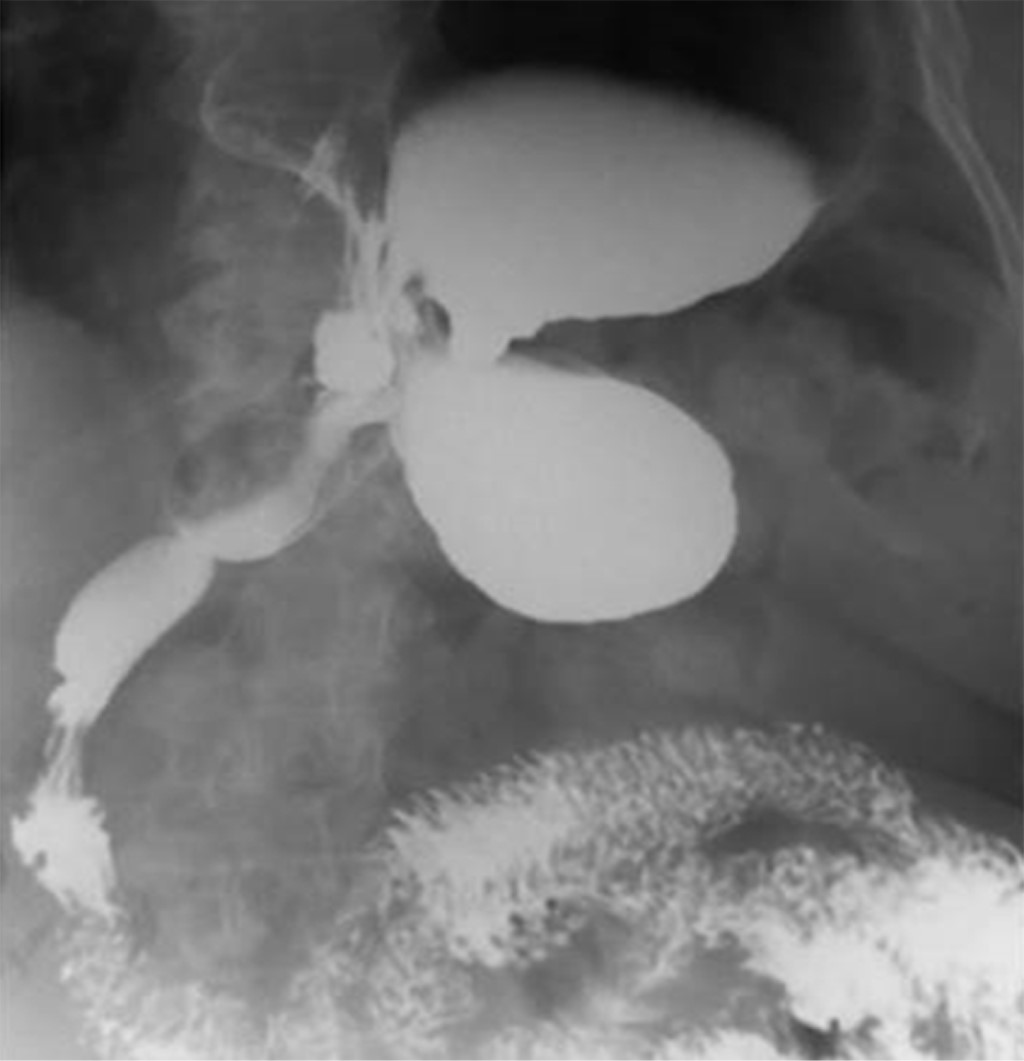

Su presentación clínica varía según la etiología, velocidad de progresión, tipo de vólvulo, el grado de rotación y obstrucción resultante, por lo que los síntomas pueden imitar cualquier cuadro abdominal. En la forma aguda, la tríada de Borchardt (distensión epigástrica severa con dolor abdominal, arcadas intratables e incapacidad para pasar una SNG) es diagnóstica en 70% de los pacientes adultos.3,10 El subagudo se caracteriza por malestar abdominal vago, mientras que en el VG crónico su sintomatología es inespecífica con dolor epigástrico, saciedad precoz, náuseas o vómito,8 otros síntomas pueden ser dolor torácico atípico, anemia, pérdida de peso, disnea, reflujo, distensión abdominal postprandial o disfagia y pueden aparecer de forma irregular durante semanas o años.7 Se debe enfatizar en la alta probabilidad de agudización del VG crónico. Las complicaciones secundarias de VG agudo son el íleo gástrico, isquemia pilórica, necrosis gástrica con perforación e incluso muerte.3,11 El diagnóstico suele ser difícil por la poca sospecha clínica, puede ir desde ser un hallazgo radiológico incidental hasta situaciones urgentes.12 En el examen con rayos X se puede detectar la dilatación gástrica con escasez de gas en la parte restante del intestino.2 Si el VG es secundario a un defecto diafragmático, el aire retrocardiaco se puede encontrar un nivel de burbuja o aire en el pecho (Figura 3), en especial en la forma mesentérico-axial la sombra gástrica muestra doble nivel de aire y fluido en bipedestación, mientras que en el órgano-axial, el estómago se coloca más horizontalmente con un nivel de fluido único.13 La serie gastrointestinal superior se considera más específica que la radiografía, pues revela obstrucción del estómago en el sitio del vólvulo y su distensión a nivel del diafragma (Figura 4).8 En este caso, la presentación no fue la clásica, por lo cual no se logró un diagnóstico certero preoperatorio. Fue necesario realizar una tomografía axial computada (TAC), lo cual concuerda con el estudio de Mazaheri y colaboradores, donde se apoya su uso como el estudio de mayor sensibilidad y especificidad para el diagnóstico de VG, con una precisión de 90%, el hallazgo más importante es el punto de transición del pico pilórico,14 confirma el diagnóstico con detalles anatómicos y posibles condiciones asociadas (hernias paraesofágicas, diafragmáticas, eventración diafragmática). En la etapa tardía del VG, el compromiso vascular puede resultar en hallazgos de isquemia gástrica, ulceración o fisuras de la mucosa gástrica.11,15 El estado hemodinámico de nuestra paciente no permitió que se realizaran más estudios y se prosiguió con la laparotomía exploradora. El tratamiento puede ser conservador o quirúrgico dependiendo de la presentación clínica y de las posibles anomalías asociadas. Mientras que en fase aguda debe tratarse con intervención quirúrgica de emergencia, no hay pautas claras sobre el manejo del VG crónico.11,14 El manejo inicial debe ser con descompresión con SNG, seguida de cirugía para comprobar la viabilidad gástrica, resecar si hay necrosis y realizar tratamiento quirúrgico definitivo: reducción de la rotación, gastrostomía, gastropexia y reparación de los defectos predisponentes.17 En un estudio retrospectivo sobre pacientes con VG y manejo conservador a cinco años, se encontró que la recurrencia sintomática fue de 64%, pero ésta sólo es una opción para los pacientes con VG crónico, en especial los mayores de 60 años y con alto riesgo quirúrgico,17 implica reducción o gastrostomía endoscópica percutánea más tratamiento procinético y antisecretor; sin embargo, existe un riesgo alto de perforación gástrica.16 En el caso presentado, se determinó que la paciente no era candidata para este manejo.1,18 La cirugía mínimamente invasiva, como la desrotación endoscópica y la cirugía laparoscópica de una sola incisión, ha ganado terreno sobre las técnicas clásicas debido a la menor tasa de complicaciones, de sangrado y de estancia hospitalaria, por eso es necesario establecer un procedimiento estándar bajo esta técnica. Habría que considerarse desde el inicio la opción de un manejo más drástico con la realización de una gastrectomía total con anastomosis esofagoyeyunal término-terminal, tratando de evitar las complicaciones, el riesgo de infección y el trauma quirúrgico repetitivo.12

Figura 4